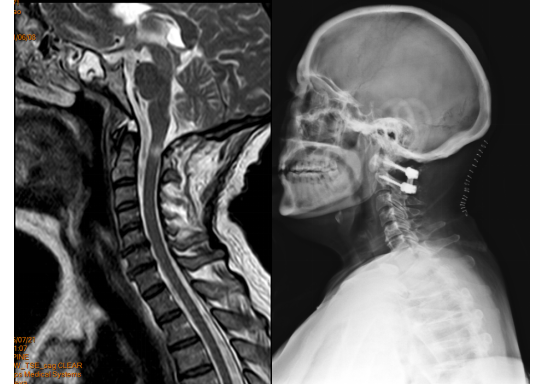

患者阿某,患有枕颈部肿瘤,四肢肌力因肿瘤压迫而下降至3级,日常生活能力受到严重影响。尽管在其省内多家医院寻求治疗,但由于病情复杂,多家医院均拒收并建议其前往北京等大城市寻求更高水平的医疗援助。

然而,患者因家庭经济条件困难,无法承受长途跋涉和高昂的医疗费用,在绝望时找到米明珊教授。

经过米明珊专家团队的详细检查和诊断,确诊为枕颈部肿瘤,并力排众议,与家属进行深入沟通后进行手术。

颈椎管和枕颈部的结构复杂,肿瘤生长部位邻近呼吸生命中枢,与周围组织的粘连较重,手术风险难度可想而知,米明珊专家团队克服了重重困难,经过4小时25分钟的紧张的显微镜下手术,成功将肿瘤全部切除。出血仅有350ml。

▲原肿瘤已切除,解除压迫

术后,患者在医护人员的精心照料下,经历了25天的康复期,重新学会了站立,成功地从病房迈步前行。家属们激动得热泪盈眶,他们紧紧握住医生的手,不停地道谢。

枕颈部肿瘤切除手术一直被视为医学领域的一大难题,米明珊专家团队用自己的智慧和勇气,为患者开辟了一条新的生命之路。